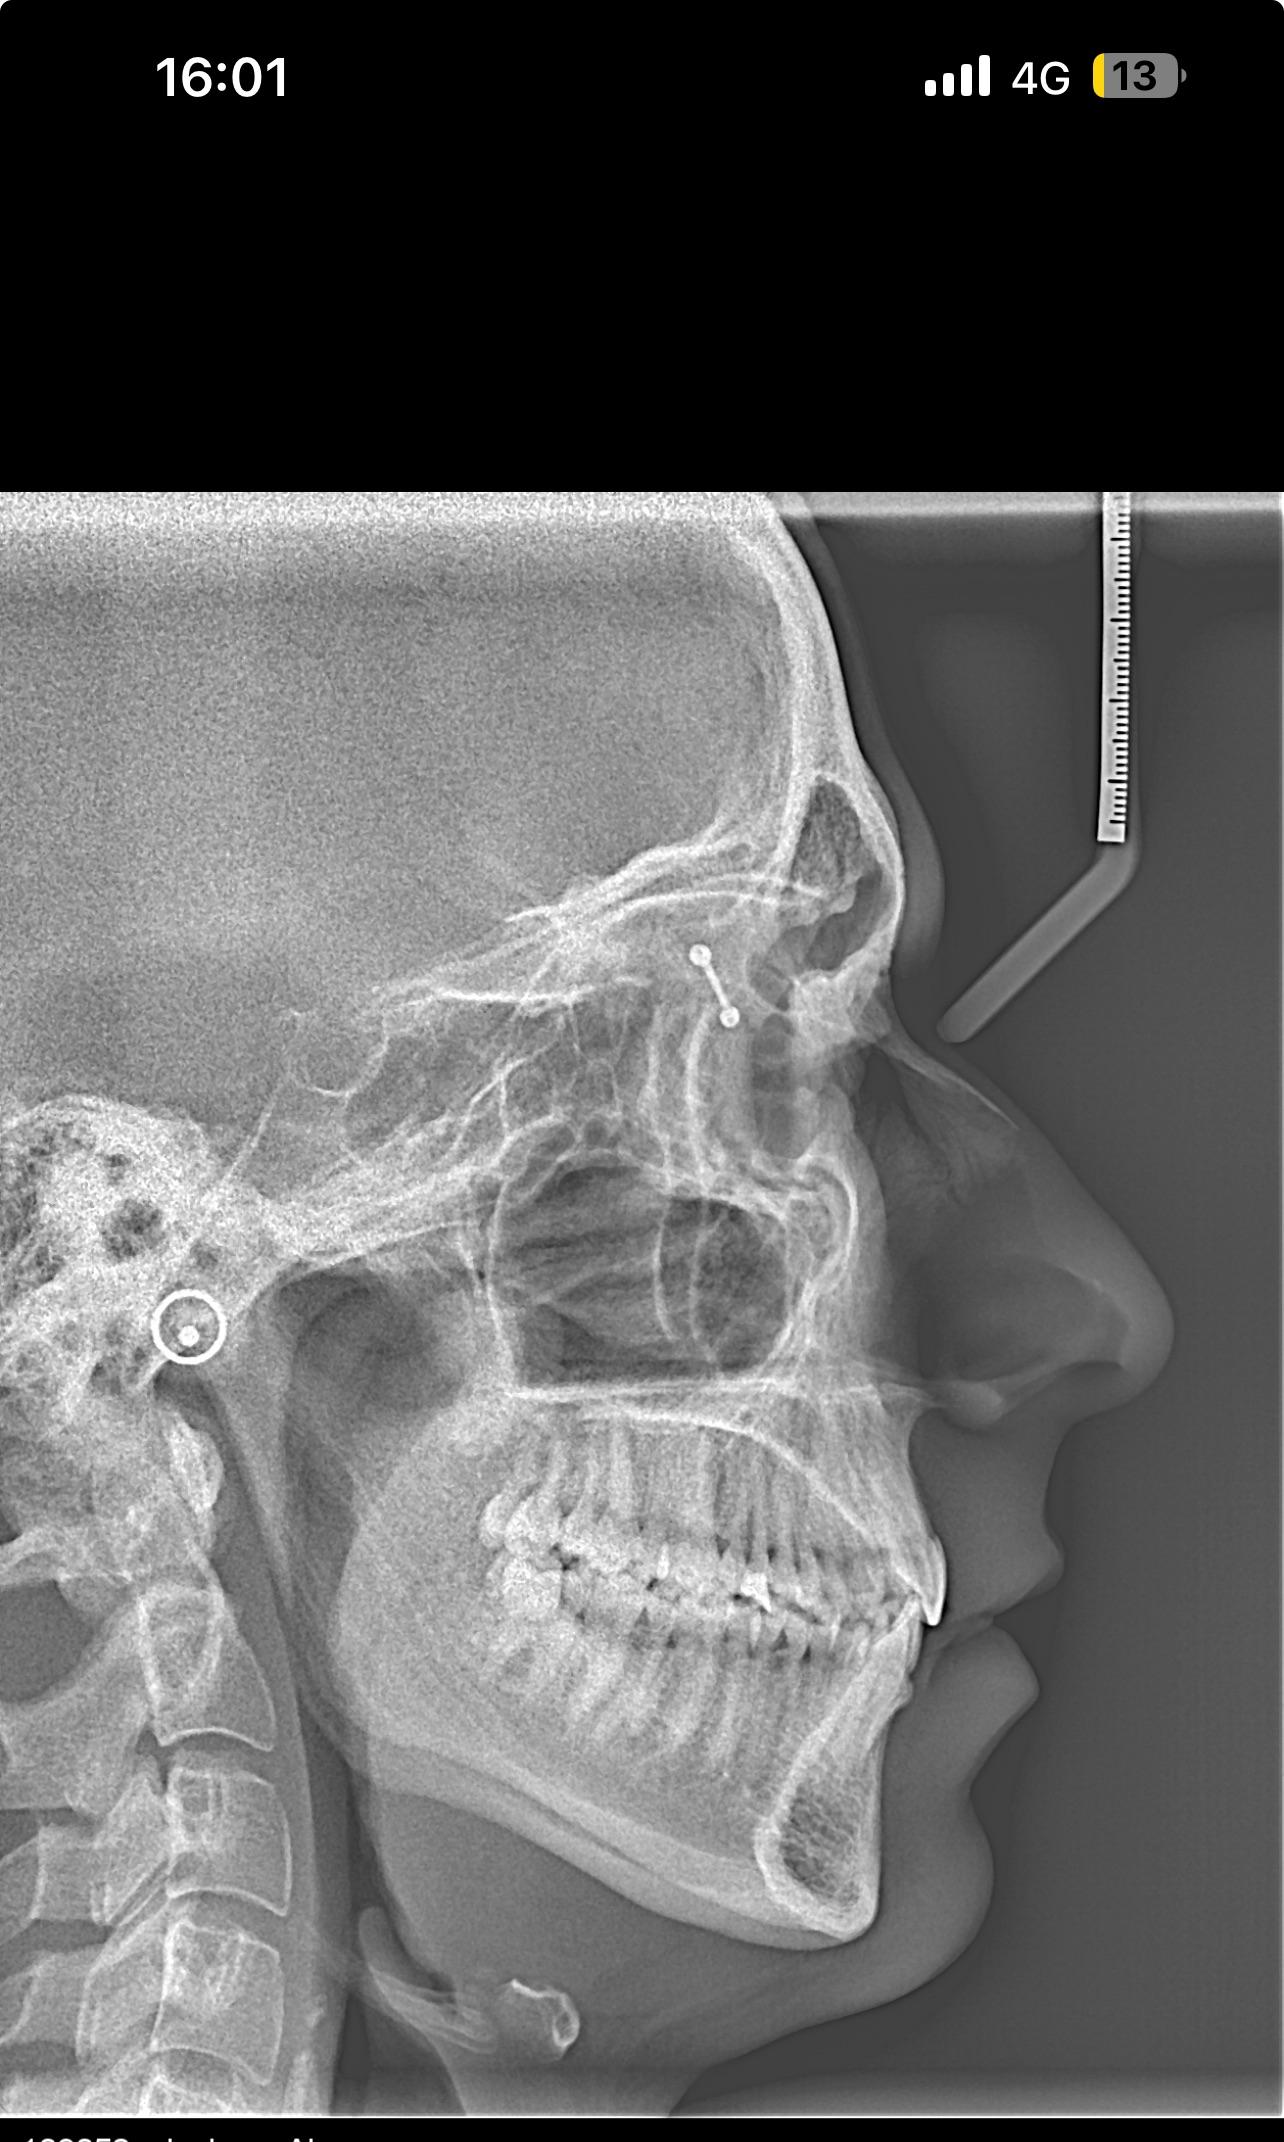

Hello, I’m looking for advice on genioplasty vs DJS. I was planned for a genio 7mm horizontal and squaring of chin on may 11th. I got a second opinion because I thought the oralmaxillofacila surgeon doing my genio might have been downplaying my mandible/maxilla recession. The second opinion oomfs surgeon said that genio would only be a camouflage and for my high expectations, might disappoint me, and I’m starting to think it will. My midface is flat and my mandible from side profile looks short and awful. The problem I have is DJS is a huge commitment for a bigger gain in a year-year and a half time. It’s a lot to take in. But I really don’t want to live my whole life with recessed jaws, I don’t want a soft youthful boyish look especially because I’m getting into my mid 20s, I hate my side profile a lot. Genio will help but I’m extremely worried I’ll be really disappointed, and I can’t really go back if I commit. Looking for advice on if I should go with the genio, see improvement now (which I care a lot about) and get a rhino/septoplasty to fix my deviated septum and be capped by by midface/mandible recession but decently improved, or If I should look awful for another year and a half with braces and my current recession but have the functional and aesthetic benefit of djs at the end. I have extremely bad breathing issues especially during exercise and pretty bad sleep issues, but I don’t know how much to that is down to allergies/deviated septum as opposed to airway issues. I just don’t know what to do, I’ll include my ceph/ct scans and side/front profile photos, would really appreciate guidance on what to do, was thinking of frauding with filler for a year before getting djs, or getting real structural change through rhino braces and genio that would all be down within 7-9 months, thankyou .

• IMG_3952.jpeg

IMG_3952.jpeg

1.5 MB · Views: 0